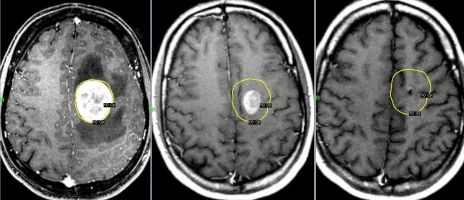

Хірургічне лікування внутрішньомозкових пухлин

Провідним методом для лікування внутрішньомозкових церебральних новоутворень залишається їх хірургічне вилучення. У нашому відділенні вилучення пухлин головного мозку проводиться під операційним мікроскопом, із застосуванням мікроінструментарію, багатофункціонального електрокоагулятора, медичного рубінового лазера.

Доброякісні внутрішньомозкові новоутворення півкуль головного мозку, як правило, можуть бути видалені в повному обсязі, тобто радикально, за умови, що пухлина не знаходиться у функціонально важливій, і, або глибинній зоні й ризик її повного видалення не переважає очікуваного позитивного ефекту в аспекті виживання і якості життя пацієнта після операції.

Тотальне видалення злоякісних гліальних пухлин мозку найчастіше неможливо у зв’язку з їх значним проростанням в навколишню мозкову тканину, ризику пошкодження життєво важливих зон мозкової тканини та кровоносних судин.

Видалення метастатичних церебральних пухлин (операція) можливо, якщо вони являються одинокими та розташовані в доступній для вилучення зоні.